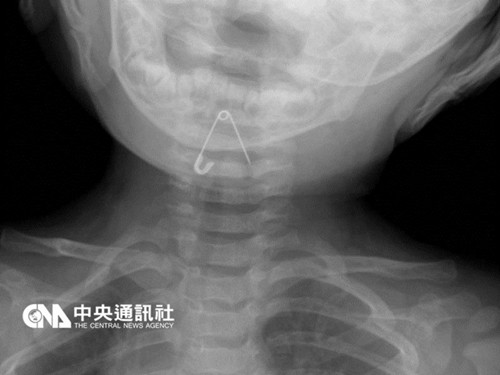

中新网11月4日电 据台湾“中央社”报道,台湾一名10个月大的刘姓男婴不慎误食新衣服的吊牌别针,父母发现孩子出现异状,赶忙将他送医,照X光赫然发现,有一枚3公分长的别针刺进男婴的喉咙,紧急取出,幸无大碍。

丰原医院小儿科医师马瑞杉表示,男婴到院时出现呕吐状况,分析应是有异物卡住喉咙,透过X光检查,赫然发现,有枚打开的别针卡在男婴的喉咙,针头还刺进声带。

马瑞杉表示,幸好别针卡的不深,不必开刀就能取出,医师先替男婴施打镇静剂,利用喉头镜伸入嘴巴,挑开会厌,再以长夹子将别针挑出。

马瑞杉指出,男婴仅受到针头轻微刺伤与刮伤,若别针刺穿喉咙或气管,恐造成永久性的伤害。